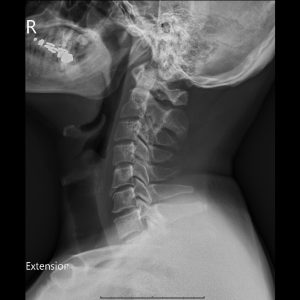

C spine Extension view